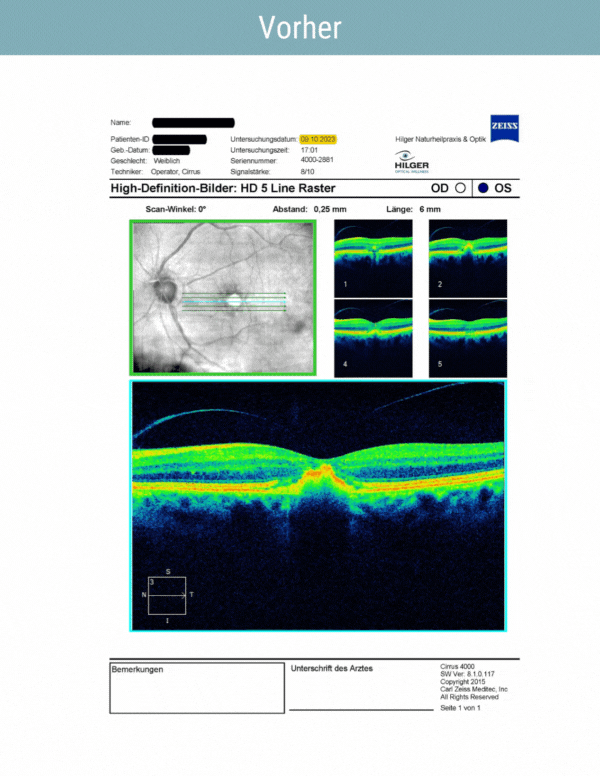

Nachweis mit bildgebenden Verfahren

Drusen vor und nach der Behandlung:

Reduzierung der hellen Drusen und Verbesserung des natürlichen Netzhautstoffwechsels

Trockene Makuladegeneration:

OCT Drusen bei trockener AMD vor Behandlung | Hilger Optiker & Naturheilpraxis in Bad Füssing

Hilger Therapiebeispiel 1-2